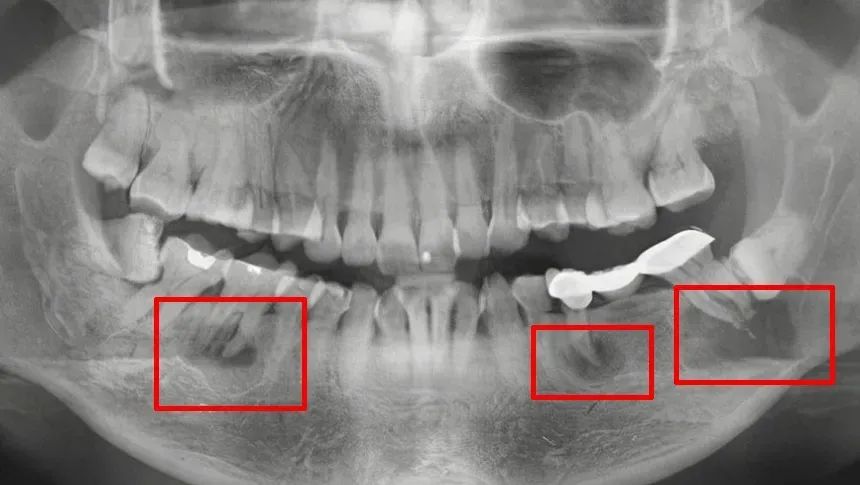

很多人觉得自己口腔全好,没有任何牙齿问题,但在牙片下,牙齿可能已经变成了这样——

▲根尖炎症,可能会引起牙槽骨骨髓炎或其他疾病。

▲阻生智齿,可能会造成冠周炎或损坏相邻牙。

▲根尖囊肿,会引起周围骨质的吸收,脸部会慢慢出现畸形的状态。